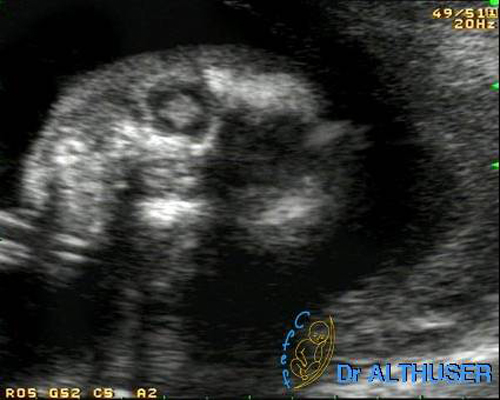

b) Echographie

La gravité de l'infection fœtale et une éventuelle indication d'interruption médicale de grossesse reposent actuellement sur l'échographie (6) et éventuellement une IRM cérébrale fœtale.

Des échographies détaillées doivent être pratiquées mensuellement pour dépister des signes évocateurs d'atteinte fœtale.

Les lésions observées peuvent être : (18)

Des calcifications parenchymateuses périventriculaires doivent être recherchées ; celles ci peuvent être isolées. Plus exceptionnellement, une atteinte ischémique peut se traduire par une porencéphalie, une encéphalomalacie multikystique ou une hydranencéphalie.

Une microcéphalie peut être la cause d'une toxoplasmose congénitale,

Un examen échographique normal n'élimine pas ne toxoplasmose congénitale évolutive. Les choriorétinites ne sont pas accessibles au diagnostic échographique.

L'IRM fœtale est un examen très utile, en complément de l'échographie, pour dépister ou préciser des lésions cérébrales. Certaines équipes, dont la notre, ont l'habitude de la proposer quel que soit le terme s'il existe un doute échographique et de façon systématique aux alentours de 32 SA.